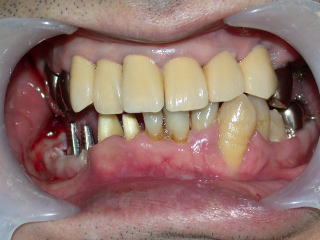

保険内診療で歯石を取り、保存不可能な歯を抜歯し、詰め物、かぶせ物も終わりました。

約半年後の平成20年2月、右下に入れ歯を作るところまで診療が進みました。

患者さんから入れ歯はいやなのでインプラントにしたいとの申し出がありました。